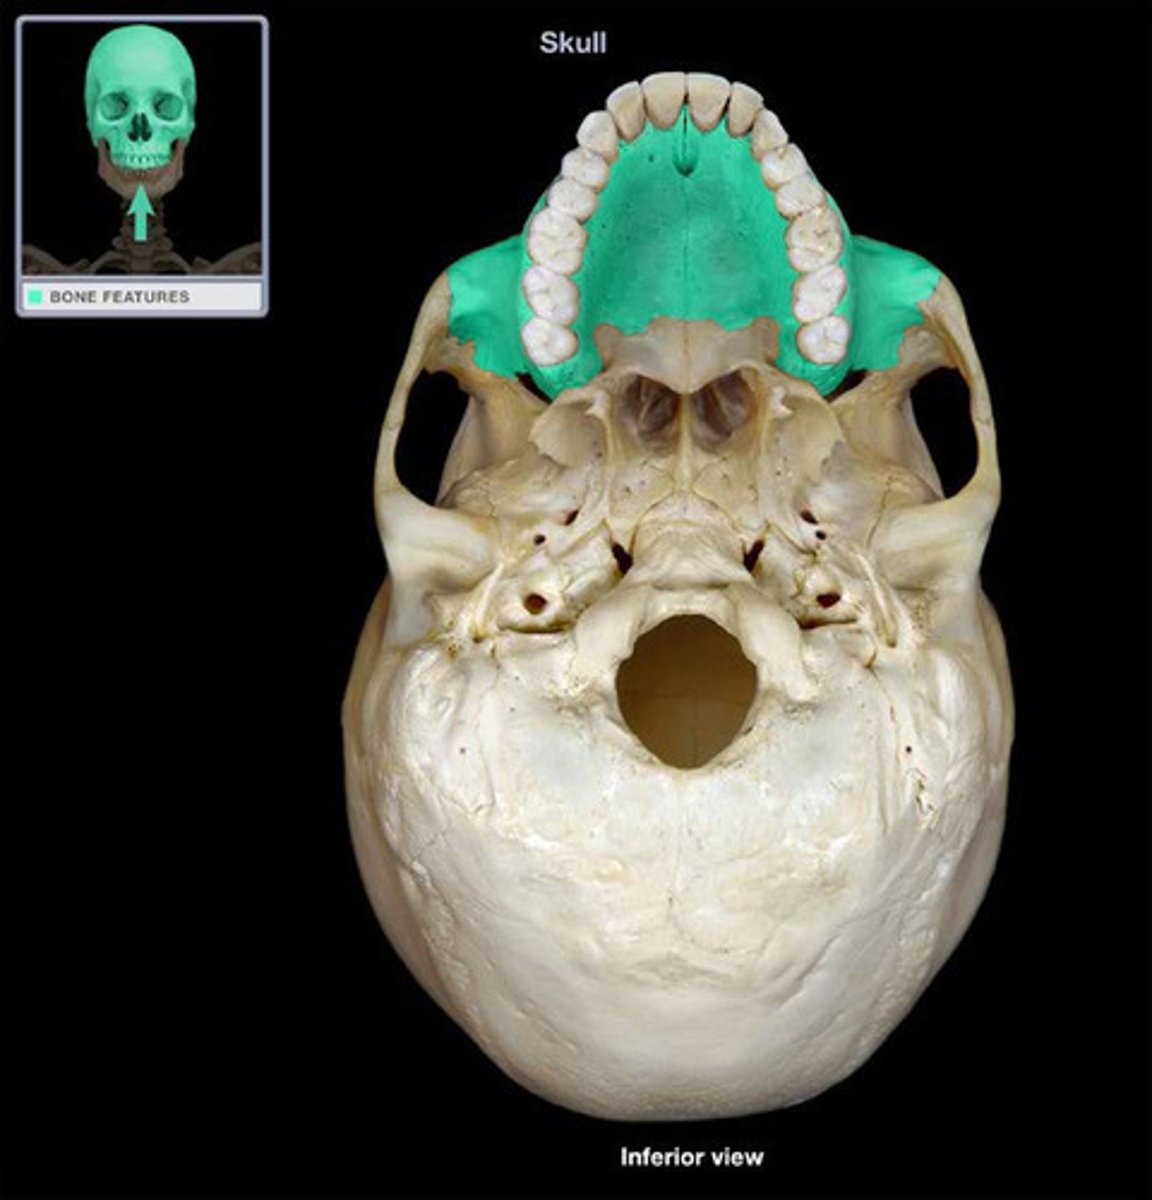

Maxilla

Maxilla

Maxilla

Palantine Bone

Incisive foramen

Alveolar processes